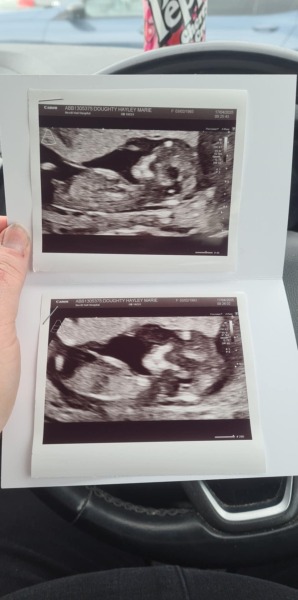

Feliciacat · 21/04/2025 09:38

The first image is 12 weeks and the second is 11 weeks. The baby is not cooperative so neither scan has a visible nub. Ironic when I like playing nub theory so much.

Due October 2025